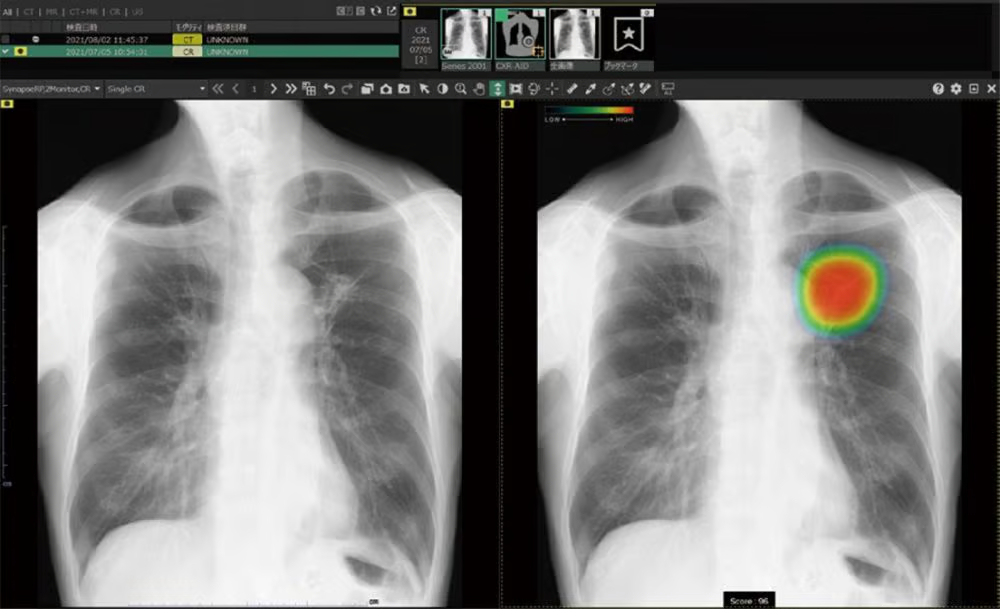

具体的な事例として、富士フイルムの「CXR-AID」は、胸部レントゲン画像から肺がんや肺炎などの異常陰影を検出する画像診断支援AIです。このシステムは、76種類の異常所見を検出でき、医師の読影をサポートします。実際の臨床現場で使用した結果、見落とし率が約20%減少したという報告があります。